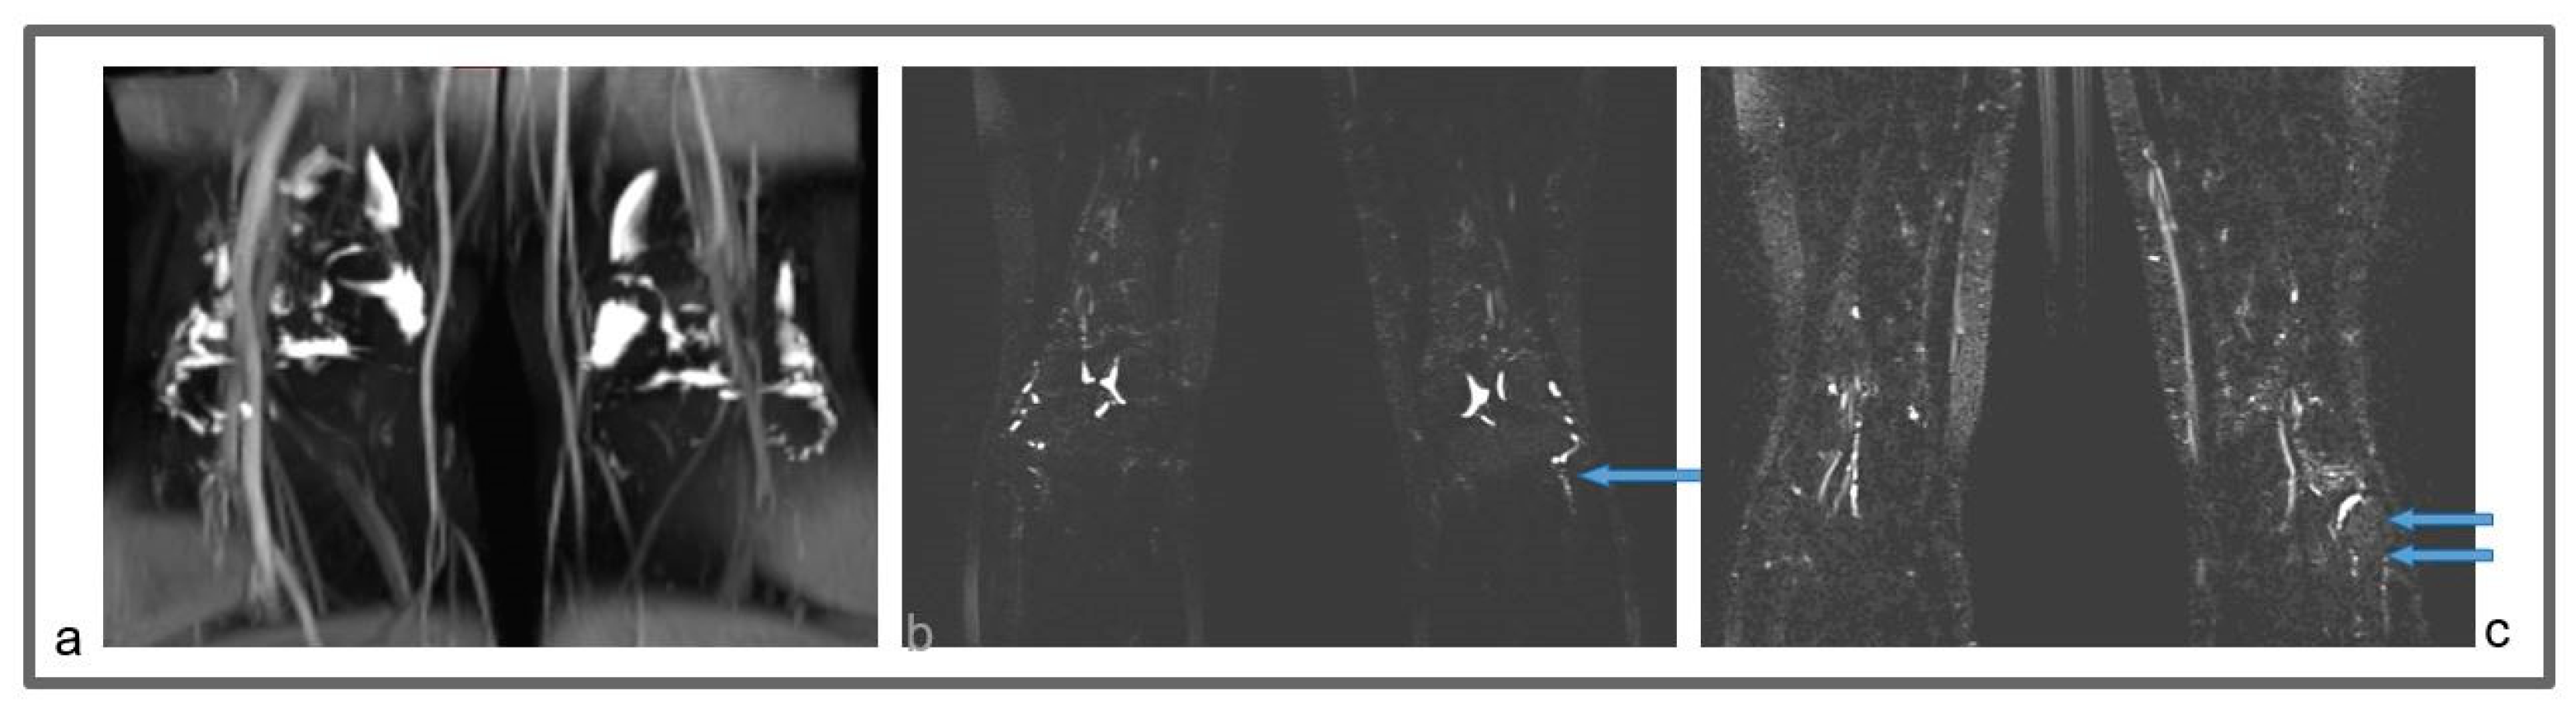

Figure 8.

Patient 3. (a) Preoperative non-contrast MR lymphography (a) (based on high-resolution heavily T2-weighted coronal sequences (turbo spin echo with repetition time 2870 ms, echo time 797 ms, field of view 380 × 380 mm, matrix 358 × 384, slice thickness 1 mm) and follow-up non-contrast MR lymphography (b,c) 1 year post-surgery. Follow-up (b,c) imaging shows the presence of new lymphatic vessels (blue arrows), not recognizable at the preoperative exam (a).